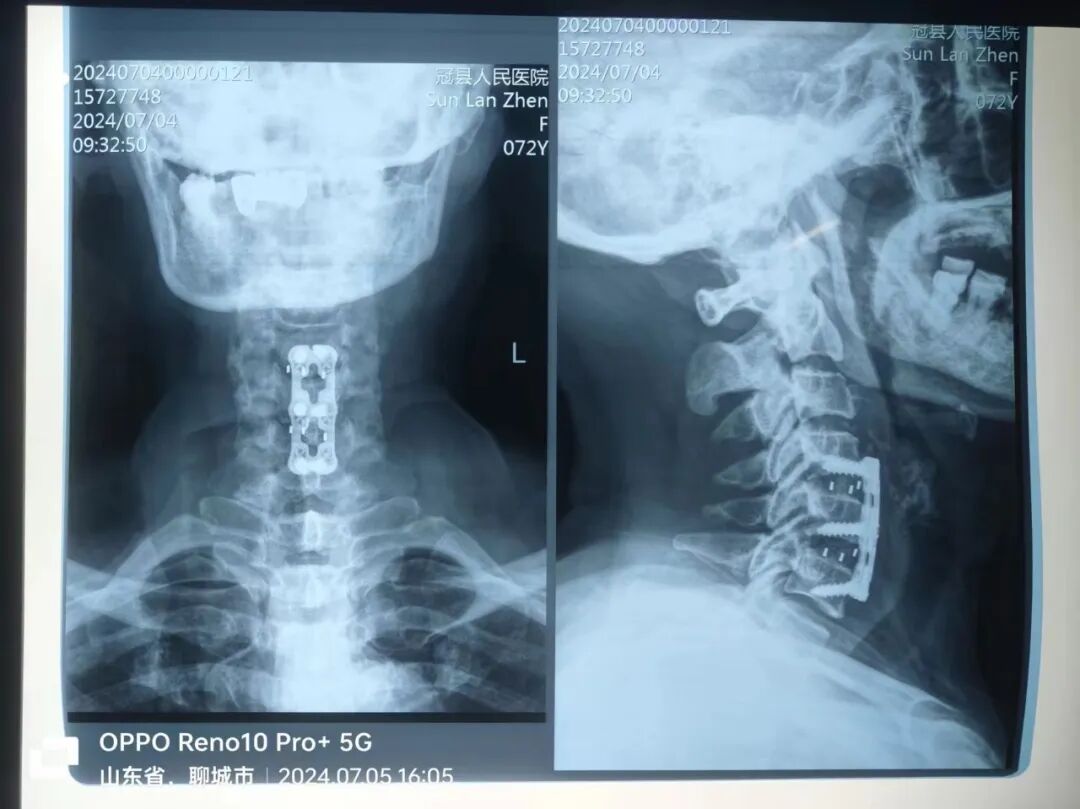

近日,冠縣人民醫(yī)院骨二科團隊成功完成在微創(chuàng)脊柱內(nèi)鏡下頸椎4-5、頸椎5-6雙節(jié)段頸椎間盤切除、減壓、融合內(nèi)固定術(shù),為患者解決痛苦,改善了生活質(zhì)量。

患者為72歲老年女性,因四肢麻木1月余來院治療,進行保守治療無效且癥狀逐漸加重,嚴重影響日常生活。經(jīng)骨二科副主任醫(yī)師李學(xué)雷團隊仔細詢問病史、細致查體、查閱影像治療后,確診為頸椎4-5、頸椎5-6雙節(jié)段脊髓型頸椎病、頸椎椎管狹窄、頸椎間盤突出,結(jié)合患者具體情況,決定為患者行微創(chuàng)脊柱內(nèi)鏡下切除、減壓、融合內(nèi)固定術(shù),術(shù)后患者癥狀明顯減輕,恢復(fù)良好,對手術(shù)治療效果非常滿意。

此次手術(shù)由我院骨二科副主任醫(yī)師李學(xué)雷醫(yī)療團隊和手術(shù)室麻醉、護理團隊全力協(xié)作完成。手術(shù)過程中,醫(yī)療團隊憑借精湛的技術(shù)和豐富的經(jīng)驗,通過微小的切口置入內(nèi)鏡,清晰地觀察到病變部位,精準地切除了突出的椎間盤組織,解除了對神經(jīng)的壓迫。